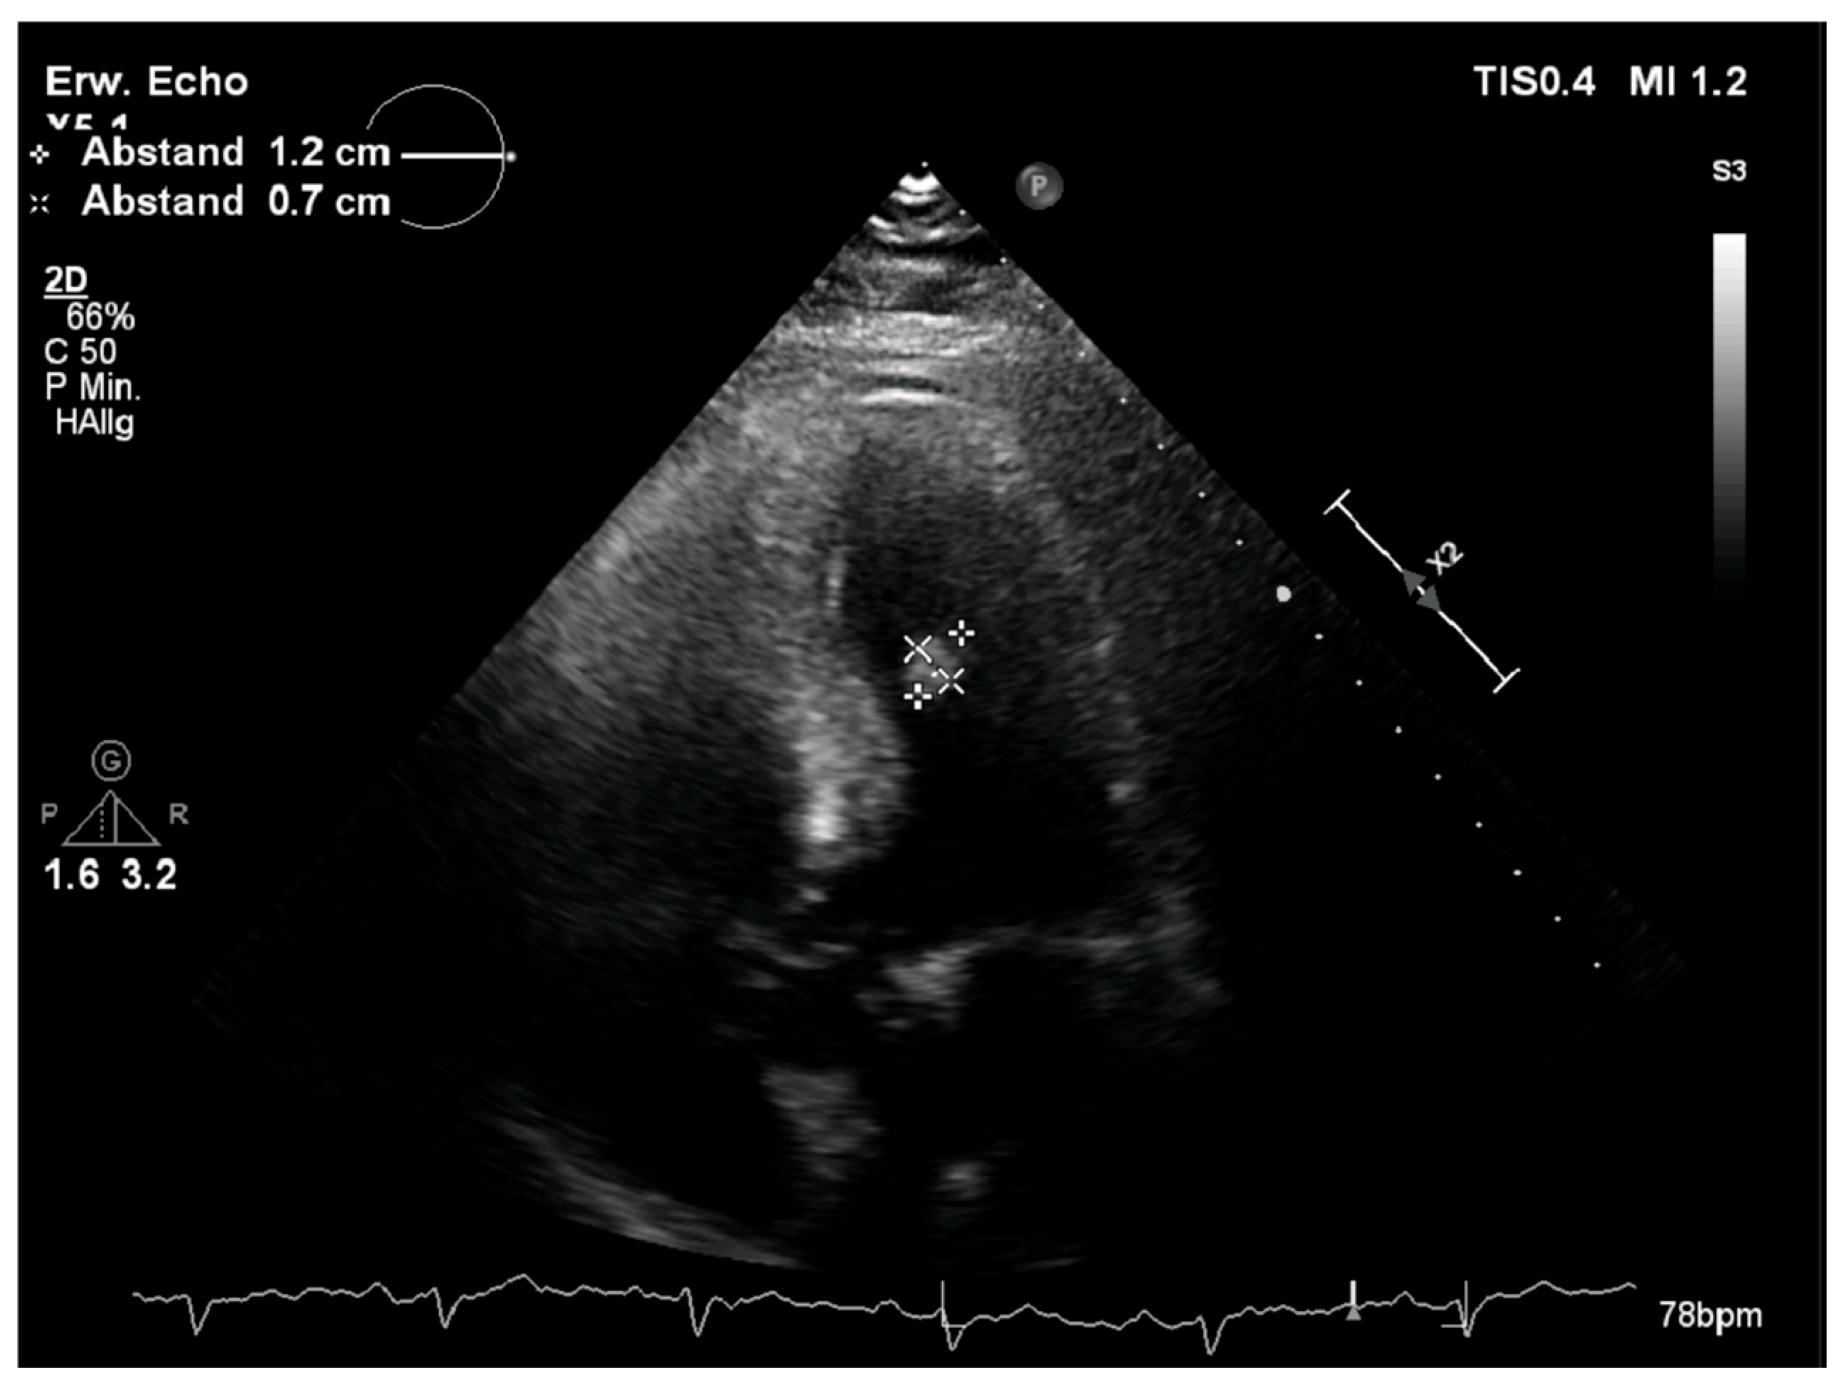

2.1. Diagnostic Assessment